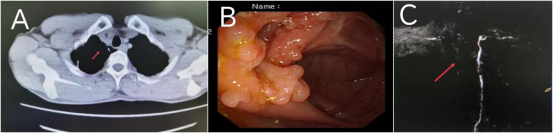

图3. 影像学检查

A图:可见纵膈稍许移位;B图:肠镜见回盲部条形白斑及颗粒样肉芽增生,表面充血肿胀;C图:胸导管成像可见胸导管颈段局部折曲角度增大。